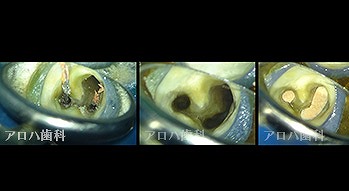

case5

左:頬側よりGP挿入。MB根尖の透過像と一致。

P根にも透過像。穿孔を疑う。

左:術前

右:術後1年

P根の穿孔封鎖

頬側の瘻孔